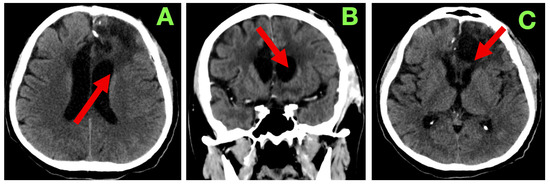

On examination, the strength of motor function was intact bilaterally with no noticeable asymmetries or fasciculations or evident fatigability in the exam. The deep tendon reflexes were symmetric and there were flexor responses on the Planta response testing. Gait and coordination were normal on testing. On language examination, the patient showed fluent expressive output with mild anomia, but observed accuracy with respect to syntax, repetition, and reading comprehension. On cognitive assessment there was intact short-term memory, attention span, and executive function testing. As part of standard follow-up, a non-contrast cranial CT (Figure 3) was completed at 3 months. This scan showed a stable post-operative cavity without any new enhancement in the cavity or hemorrhagic complication or indication of any new hydrocephalus. There was also considerable reduction in perilesional edema. The ventricular appearance had returned to their apparent normal appearance, with no evident midline shift/sub-dural collection/sub-acute delayed infarct. Relative to the original report, they interpreted the findings as consistent with radiological stability of the surgical site and that there continued no progression, particularly with the absence of any new findings.

Figure 3. Three-month post-operative cranial CT scan. (A): Axial section demonstrating a well-defined left frontal resection cavity (red arrow) with smooth margins and no residual mass effect. Compared to the immediate post-operative stage, most of the surrounding vasogenic edema has resolved. Ventricular configuration is symmetric, with no midline shift or hydrocephalus. (B): Coronal reconstruction confirming stability of the resection cavity (red arrow), with no evidence of recurrent mass lesion. Cortical–subcortical architecture around the margins remains preserved, and no abnormal extracerebral collections are present. (C): Caudal axial slice showing the inferior aspect of the resection cavity (red arrow), with basal ganglia and thalamic anatomy intact. No delayed ischemia, hemorrhage, or secondary injury is observed, and the overall appearance is consistent with post-operative stability at three months.